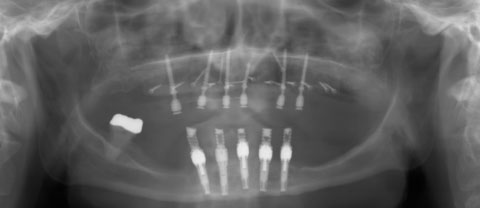

Επίσης, πλέον μία πολύ συχνή επέμβαση είναι η τοποθέτηση οστικού μοσχεύματος στα ιγμόρια άντρα για δημιουργία οστικού όγκου, με σκοπό την τοποθέτηση οδοντικών εμφυτευμάτων στην άνω γνάθο.

Αποτελεί και αυτή επέμβαση ρουτίνας για τους Στοματικούς και Γναθοπροσωπικούς Χειριουργούς, με αποτέλεσμα που αγγίζει σχεδόν πάντα το άριστο. Και εδώ το πιό συχνό αίτιο αποτυχίας, είναι το ίδιο όπως αναφέρθηκε πρωτύτερα για τους φρονιμίτες. Είναι πλέον γνωστό σε όλους ότι τα οδοντικά εμφυτεύματα συμβάλλουν στην αποκατάσταση της λειτουργίας της μάσησης, της κατάλληλης σύγκλισης και της διατήρησης  του οδοντικού φραγμο

Κάποιοι ασθενείς δεν προτιμούν τις κινητές οδοντοστοιχίες ως προσθετική αποκατάσταση, καθώς και άτομα μικρής ηλικίας με απώλεια δοντιών, η επιλογή των οδοντικών εμφυτευμάτων είναι η προτιμότερη λύση. Αλλά ακόμα και στους ασθενείς που έχουν προσαρμοστεί με τις ολικές οδοντοστοιχίες, αλλά δυσανασχετούν με την κινητικότητα αυτών πάλι τα οδοντικά εμφυτεύματα δίνουν καθοριστική λύση.